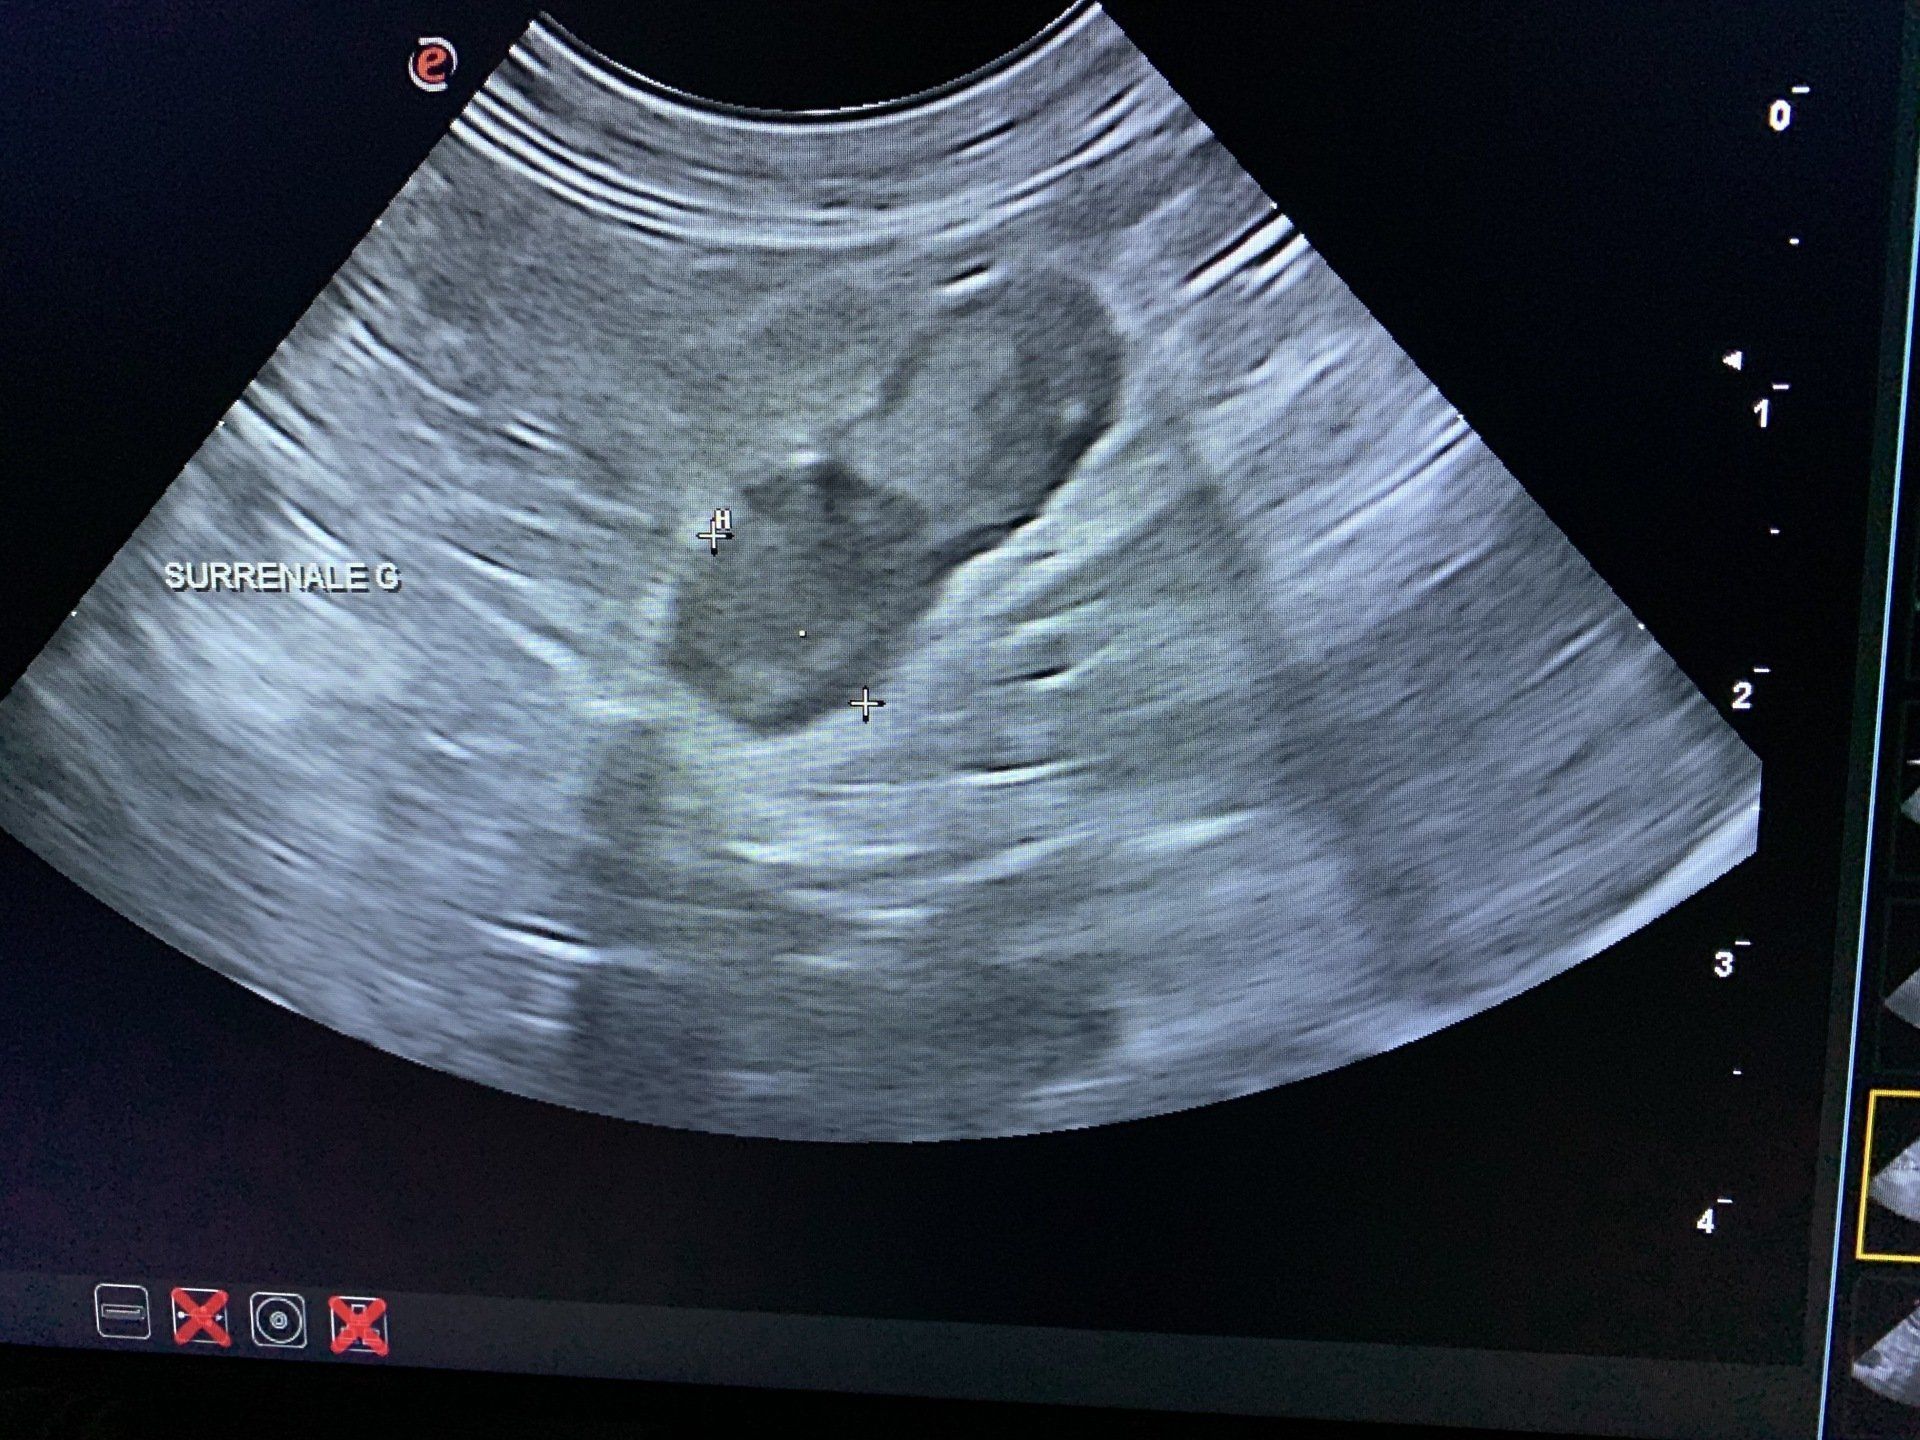

abdominale

L'échographie permet d'explorer les différents organes de l'abdomen (tissus mous) : foie, rate, reins, vessie...elle est utile pour diagnostiquer et suivre certaines pathologies. Elle permet également d'assurer le suivi de gestation.

Cytoponctions et biopsies échoguidées

Sous contrôle échographique, nous réalisons des prélèvements à visée diagnostique (ponctions à l'aiguille fine, biopsies) et le recueil d'urine de façon stérile.